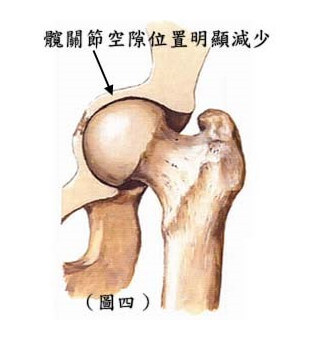

退化性髖關節炎通常只影響一邊的關節。患者初期只感到少許痛,後期慢慢進展到非常痛,尤期當 走路或活動過後或早上起來覺得髖關節緊硬,可能有時走路會拐向一方行,腿部不能內旋及關節非常 痛楚。痛楚屬於沉痛 ( 不是外面或刺痛的感覺 ),通常稍作休息後,患者又覺得好一些。從 X-光片中, 看到髖關節空隙位置明顯減少,大腿頂部增生骨剌。